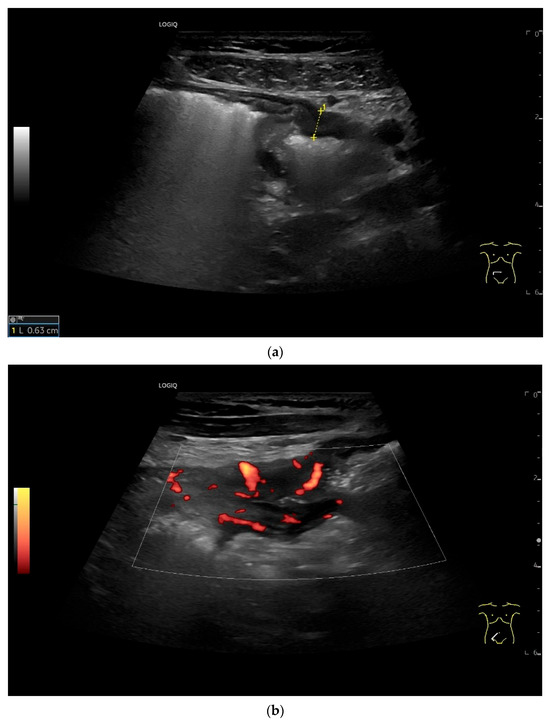

Figure 18.

Small intestine metastasis of a malignant melanoma (between the markers). Significant hypoechoic wall thickening (W) with narrowed lumen reflex (L) and lumen obstruction.

Figure 19.

Small intestine metastasis of pleural mesothelioma. Hypoechoic tumorous wall thickening (T) between the markers. The normal wall with Kerckring’s folds (KF) is visible adjacent to it. Next to the small intestine is a round hypoechoic tumor-suspicious lymph node (L).